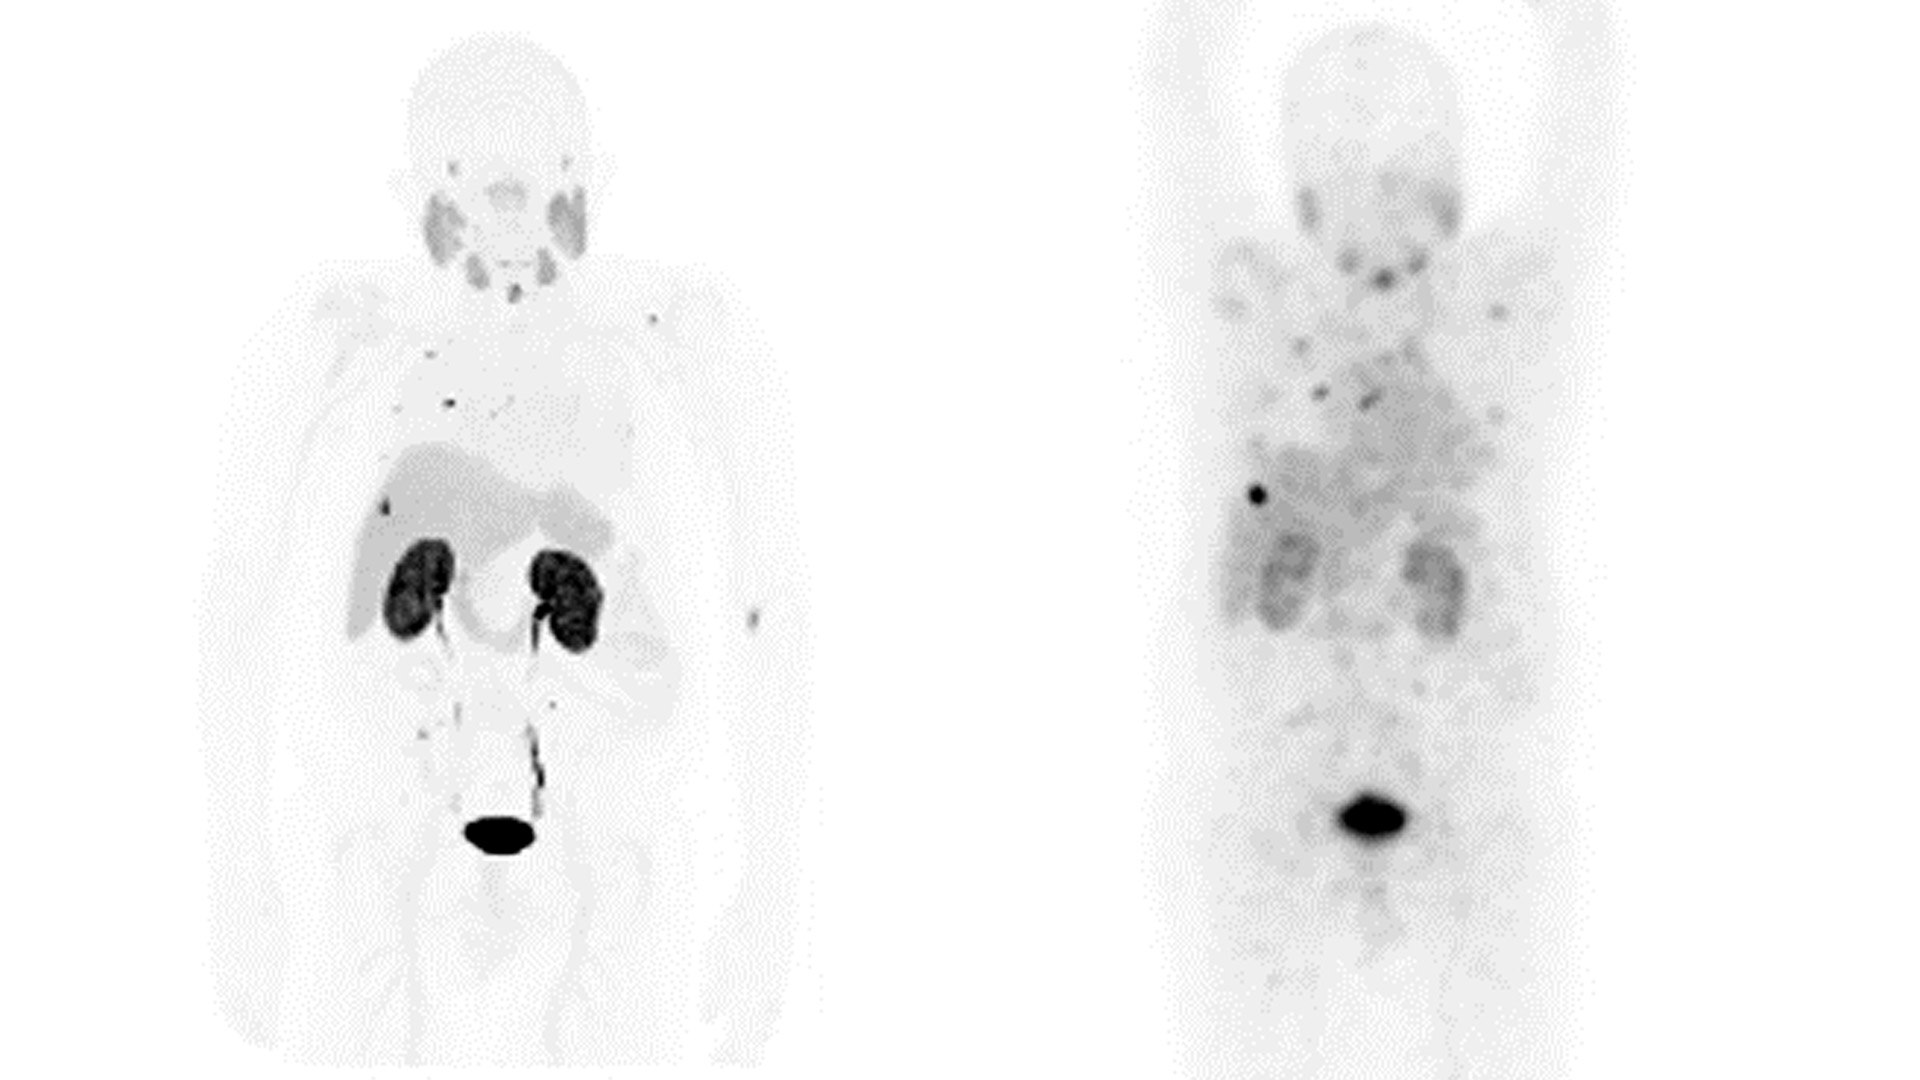

DIAGNÓSTICO

GE HealthCare es pionera en soluciones que permiten una sensibilidad y una confianza en el diagnóstico sin precedentes.

Nuestra exclusiva gama de soluciones de adquisición de imágenes para diagnóstico, centradas en la Theranostics, se ha diseñado específicamente para satisfacer las necesidades de los médicos y de sus pacientes, hoy y en el futuro.

ADQUISICIÓN DE IMÁGENES Y MONITORIZACIÓN DEL TRATAMIENTO

GE HealthCare está dando forma hoy al futuro de la Theranostics con soluciones precisas de adquisición de imágenes y monitorización, así como con innovaciones en la respuesta al tratamiento.